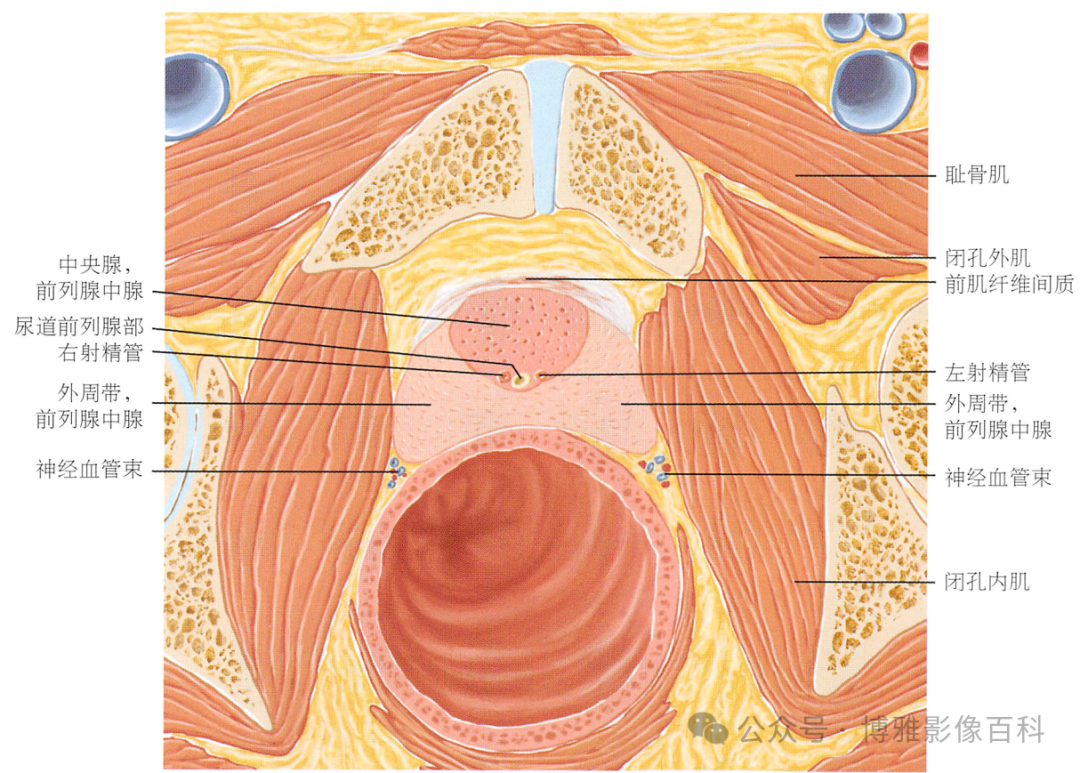

解剖学

前列腺分区解剖学

MR 解剖学